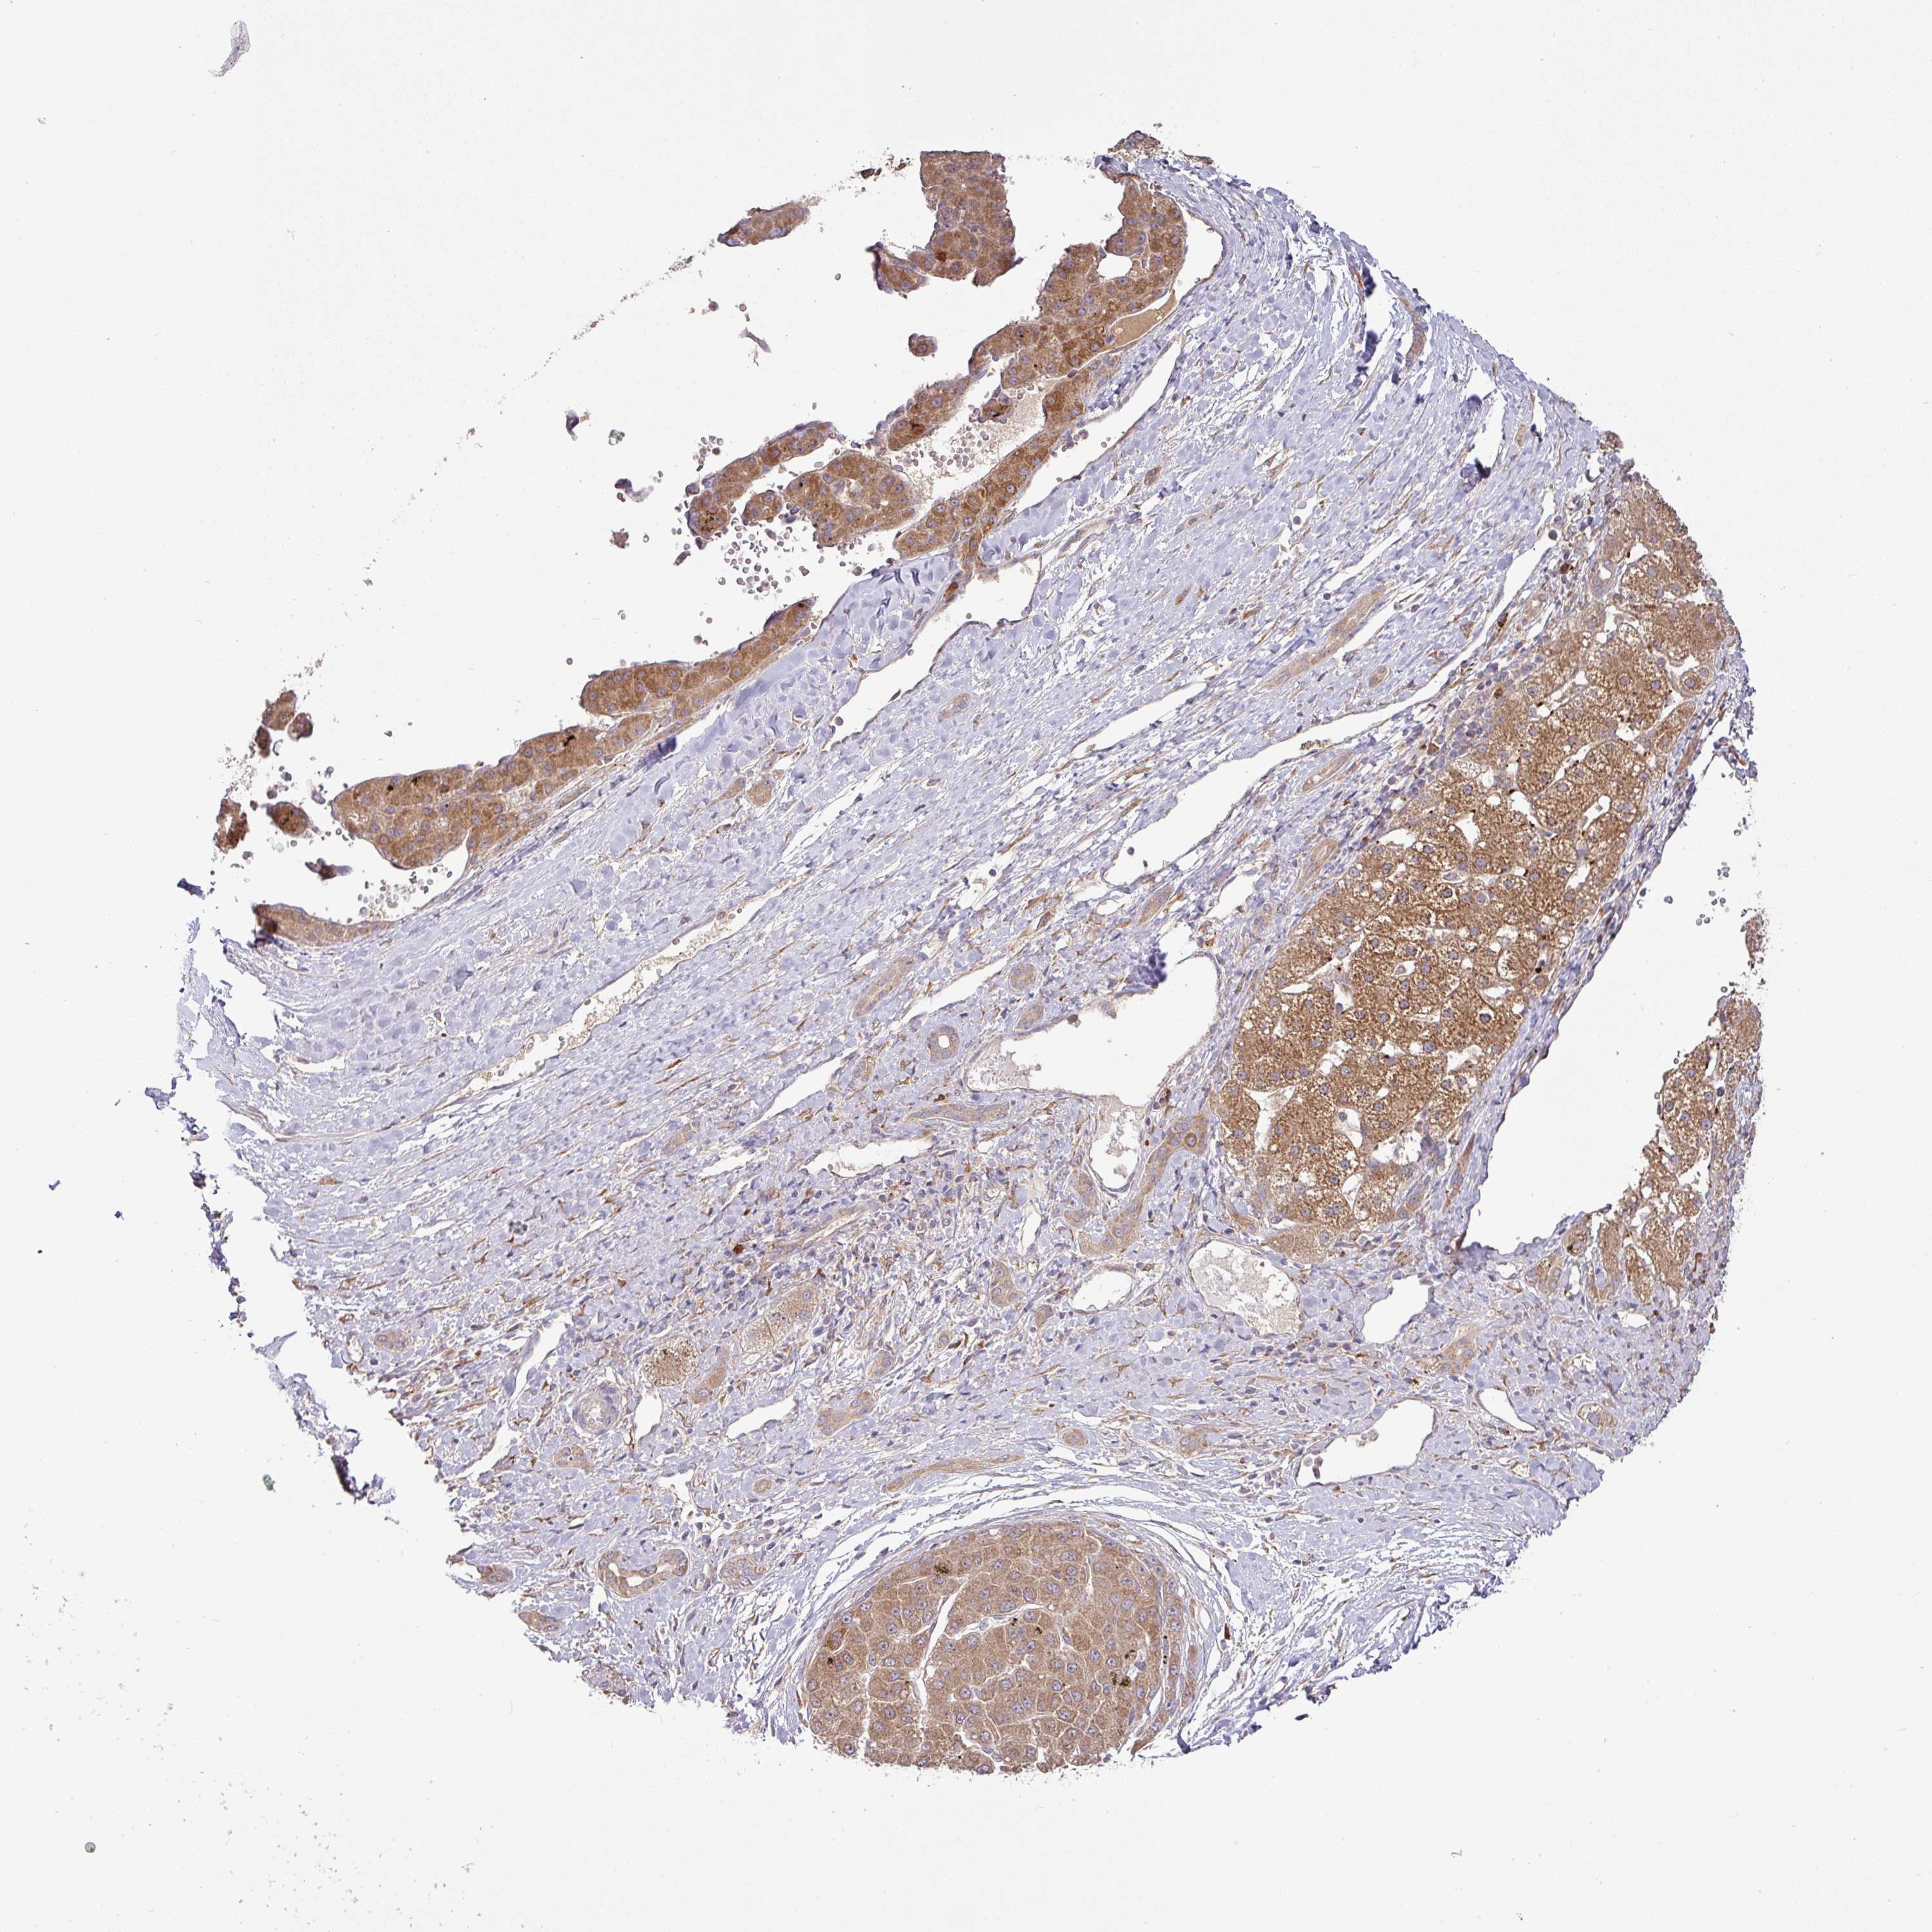

LIVER CANCER - Protein expressioni

A mouse-over function shows sample information and annotation data. Click on an image to view it in a full screen mode. Samples can be filtered based on level of antibody staining by selecting one or several of the following categories: high, medium, low and not detected. The assay and annotation is described here.

Note that samples used for immunohistochemistry by the Human Protein Atlas do not correspond to samples in the TCGA dataset.

Antibody stainingi

Antibody staining in the annotated cell types in the current human tissue is reported as not detected, low, medium, or high, based on conventional immunohistochemistry profiling in selected tissues. This score is based on the combination of the staining intensity and fraction of stained cells.

Each image is clickable and will lead to virtual microscopy that enables deeper exploration of all samples and also displays staining intensity scores, fraction scores and subcellular localization as well as patient and tissue information for each sample.

Antibody HPA053938

Staining

High

Medium

Low

Not detected

Intensity

Strong

Moderate

Weak

Negative

Quantity

>75%

75%-25%

<25%

None

Location

Nuclear

Cytoplasmic/membranous

Cytoplasmic/membranous,nuclear

Carcinoma, Hepatocellular, NOS

Cholangiocarcinoma